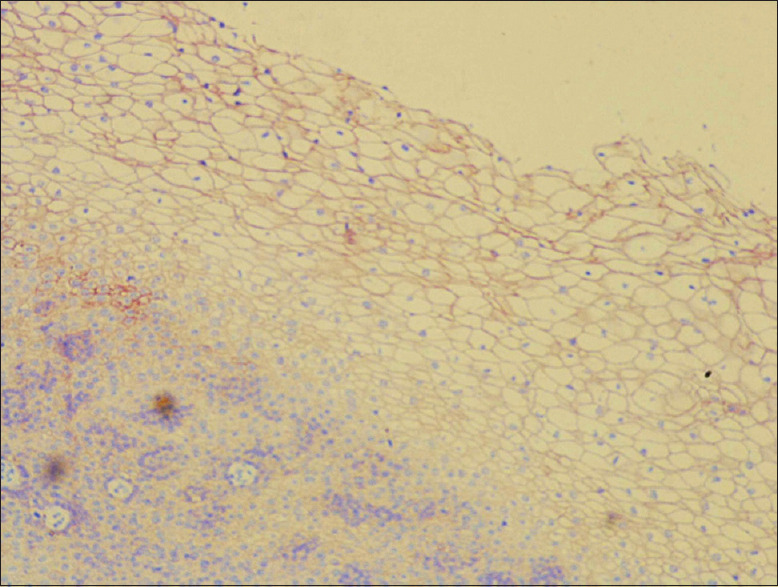

Materials and methods: A total of 50 archival lymph node blocks, both positive and negative neck nodes of the patients treated for OSCC, were used for the assessment of DSG1 and 3 expressions by immunohistochemistry (IHC) following their histopathological examination. The assessment of IHC staining was conducted by two independent maxillofacial pathologists as per the grading criteria in all the lymph node sections.

Results: A total number of 88 nodes were assessed, of which 27 were positive on histopathological assessment. DSG1 and DSG3 positivity were noted and varied between 11.4-12.5% and between 20.5-22.7% of positive nodes, respectively, between the observers. Cronbach's alpha was calculated for interobserver reliability for positive identification of metastatic lymph nodes. Area under curve (AUC) values for DSG1 were 0.478 and 0.02 for DSG3, and not so statistically significant value for DSG1 was obtained (P > 0.05) compared to DSG3 (P = 0.000).

Conclusion: Current study results do not confirm the roles of DSG1 and 3 as potential markers for occult lymph node metastasis, and hence, the reliability of their roles may require further studies along with other markers of lymph node metastasis. Even though overexpression of DSG3 and partial expression of DSG1 in OSCC is seen, further studies may be required to confirm them either as a diagnostic or prognostic marker which can be useful for future management in cases of radical neck dissections.